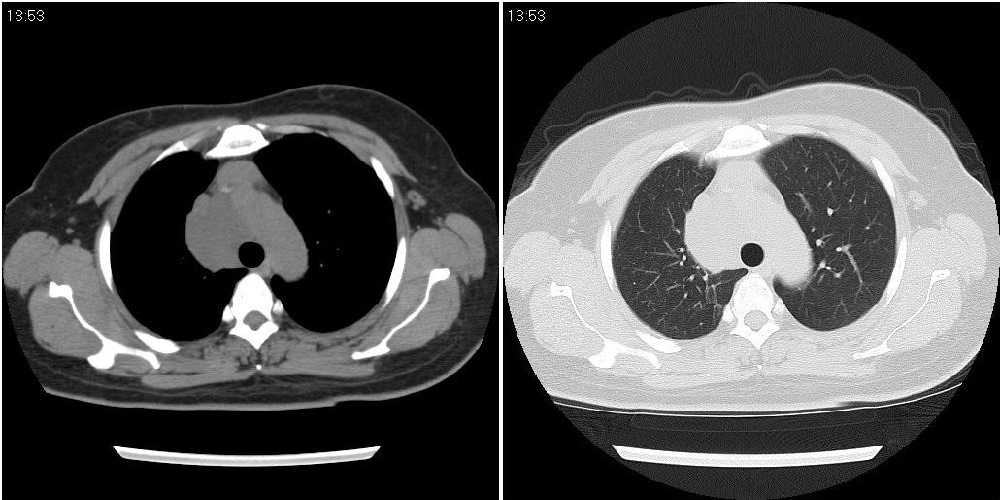

标题: CT24795:女性,47岁,右下腿静脉静脉曲张手术前体检,发现 [打印本页]

标题: CT24795:女性,47岁,右下腿静脉静脉曲张手术前体检,发现

囊性无明显占位效应:1淋巴管囊肿2畸胎瘤(其上部见小钙化)3前肠囊肿

右上纵隔囊性占位性病变;考虑淋巴管囊肿,不排除支气管囊肿。

支气管囊肿、囊性畸胎瘤、肠源性囊肿均有可能。

右上纵隔囊性占位性病变;考虑淋巴管囊肿,不排除支气管囊肿。 建议增强。

考虑淋巴管囊肿,不排除前肠囊肿。